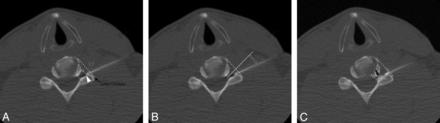

The skin is prepared and draped in a sterile fashion and is anesthetized with 1% lidocaine. With intermittent CT fluoroscopy, a 22-ga 3.5-inch needle is advanced into the skin and directed to the posterior aspect of the neural foramen, aiming for the needle tip to lie in or close to a foraminal zone location (Fig 1). A syringe containing dilute contrast (2-mL sterile saline and 1-mL iopamidol [Isovue M-200; Bristol Myers Squibb, Princeton, New Jersey]) is attached to the needle hub via a 31-inch microbore tubing (Microbore Extension Set; Cardinal Health, Dublin, Ohio). After negative aspiration, 0.2–0.5 mL of diluted contrast is slowly injected with the bevel of the needle directed ventrally. The purpose of contrast injection before steroid injection is to verify that the needle tip is not intravascular. A second role of contrast is to indicate the distribution that the subsequent steroid injection will follow. Dilute contrast was used because we have found the attenuation of undiluted contrast obscures the needle tip and makes repositioning the needle difficult.

Classification of needle location and contrast distribution in a 42-year-old man with left-neck pain who had a CT-guided CTSI of the left C6 nerve root. A, CT fluoroscopic image shows the needle tip (arrowhead) in the foraminal zone (FZ). Foraminal zone and extraforaminal (EF) locations are separated by an oblique line from the anterolateral vertebral body to the lateral margin of the facet (junctional line). When the needle tip is on the oblique line, it is considered to be a junctional location (black arrow). B, Needle angle (double-headed arrow) is measured from the needle to a line (solid white line) perpendicular to the junctional line (dotted yellow line). C, CT fluoroscopic image of the cervical spine after the injection of dilute contrast. The contrast is seen in the intraforaminal region (black arrow).

Two fellowship-trained neuroradiologists retrospectively evaluated CT fluoroscopic images from the CTSI procedures. Images were analyzed independently on a PACS workstation. A third proceduralist resolved disagreements. Readers classified the needle-tip location, measured the angle of needle approach, and classified the contrast distribution. The needle-tip location was categorized as foraminal zone, junctional, and extraforaminal. These anatomic divisions are shown on Fig 1. Foraminal zone and extraforaminal locations were separated by an oblique line from the anterolateral vertebral body to the lateral margin of the facet. When the needle tip was on the oblique line (outer margin of the neural foramen), it was considered to be a junctional location. The needle angle was measured relative to the longitudinal axis of the neural foramen (Fig 1).

The distribution of contrast was classified as ≥1 of the following: intraforaminal, extraforaminal, central epidural (intraspinal canal) regions, and “other” (Figs 1⇓–3). “Other” regions included intravascular and subperiosteal contrast.